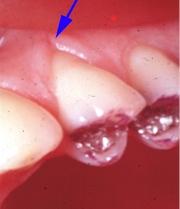

La gingivite localisée peut avoir pour cause des malrelations dento-dentaires.

Une simple fissure gingivale doit mettre le praticien en éveil.